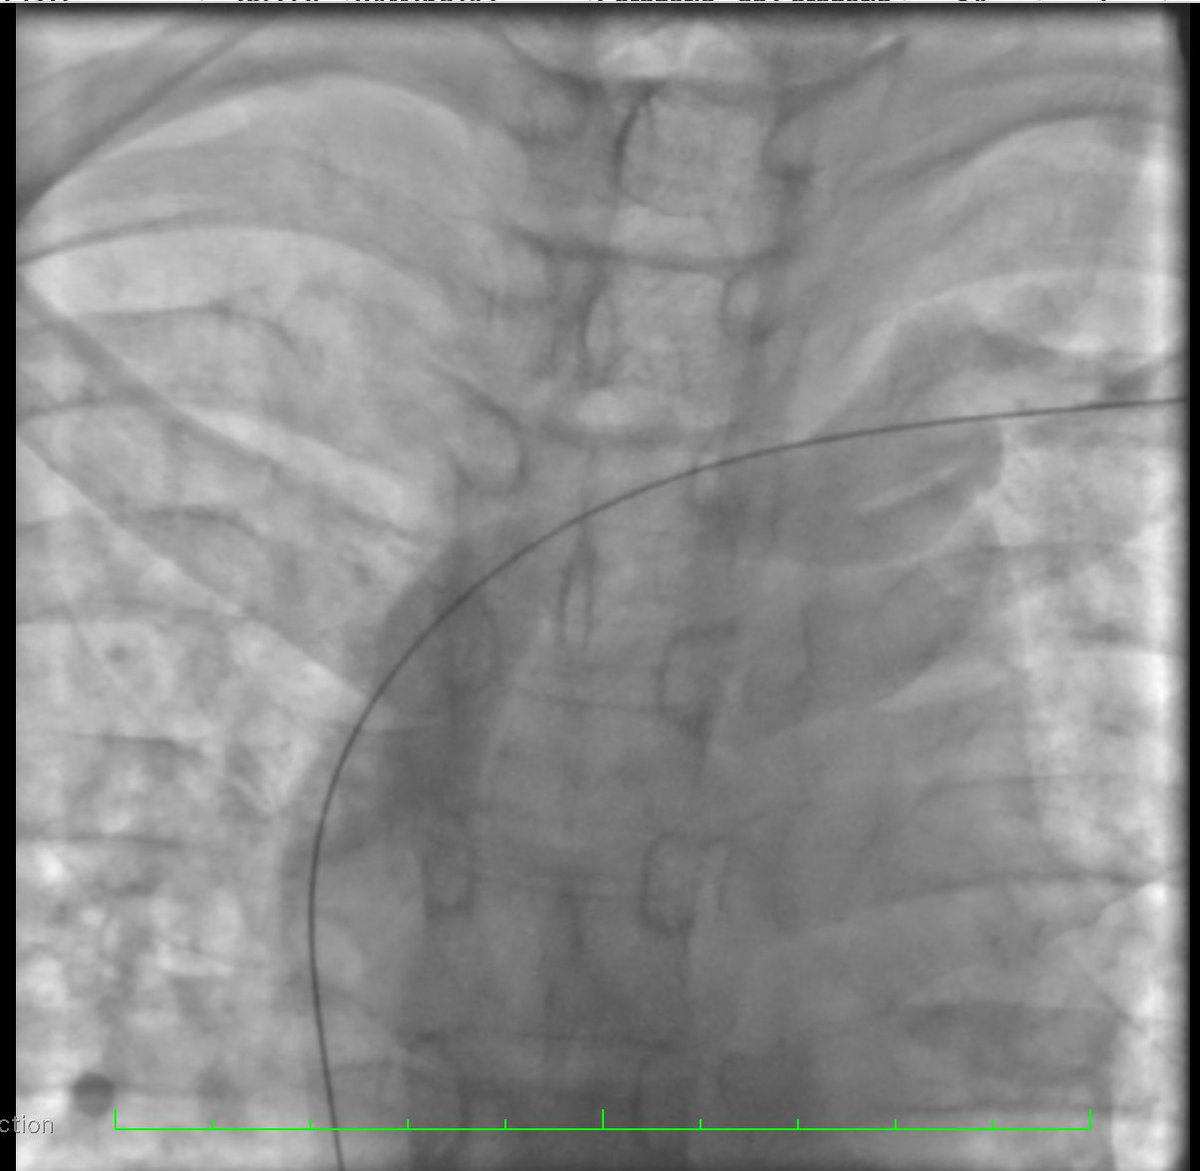

Colocación de Catéter Tenckhoff percútaneo con técnica Seldinger Servicio de Nefrología HGR 46 ✅Menor estancia hospitalaria ✅Menor riesgo de complicaciones ✅Uso temprano de cavidad peritoneal